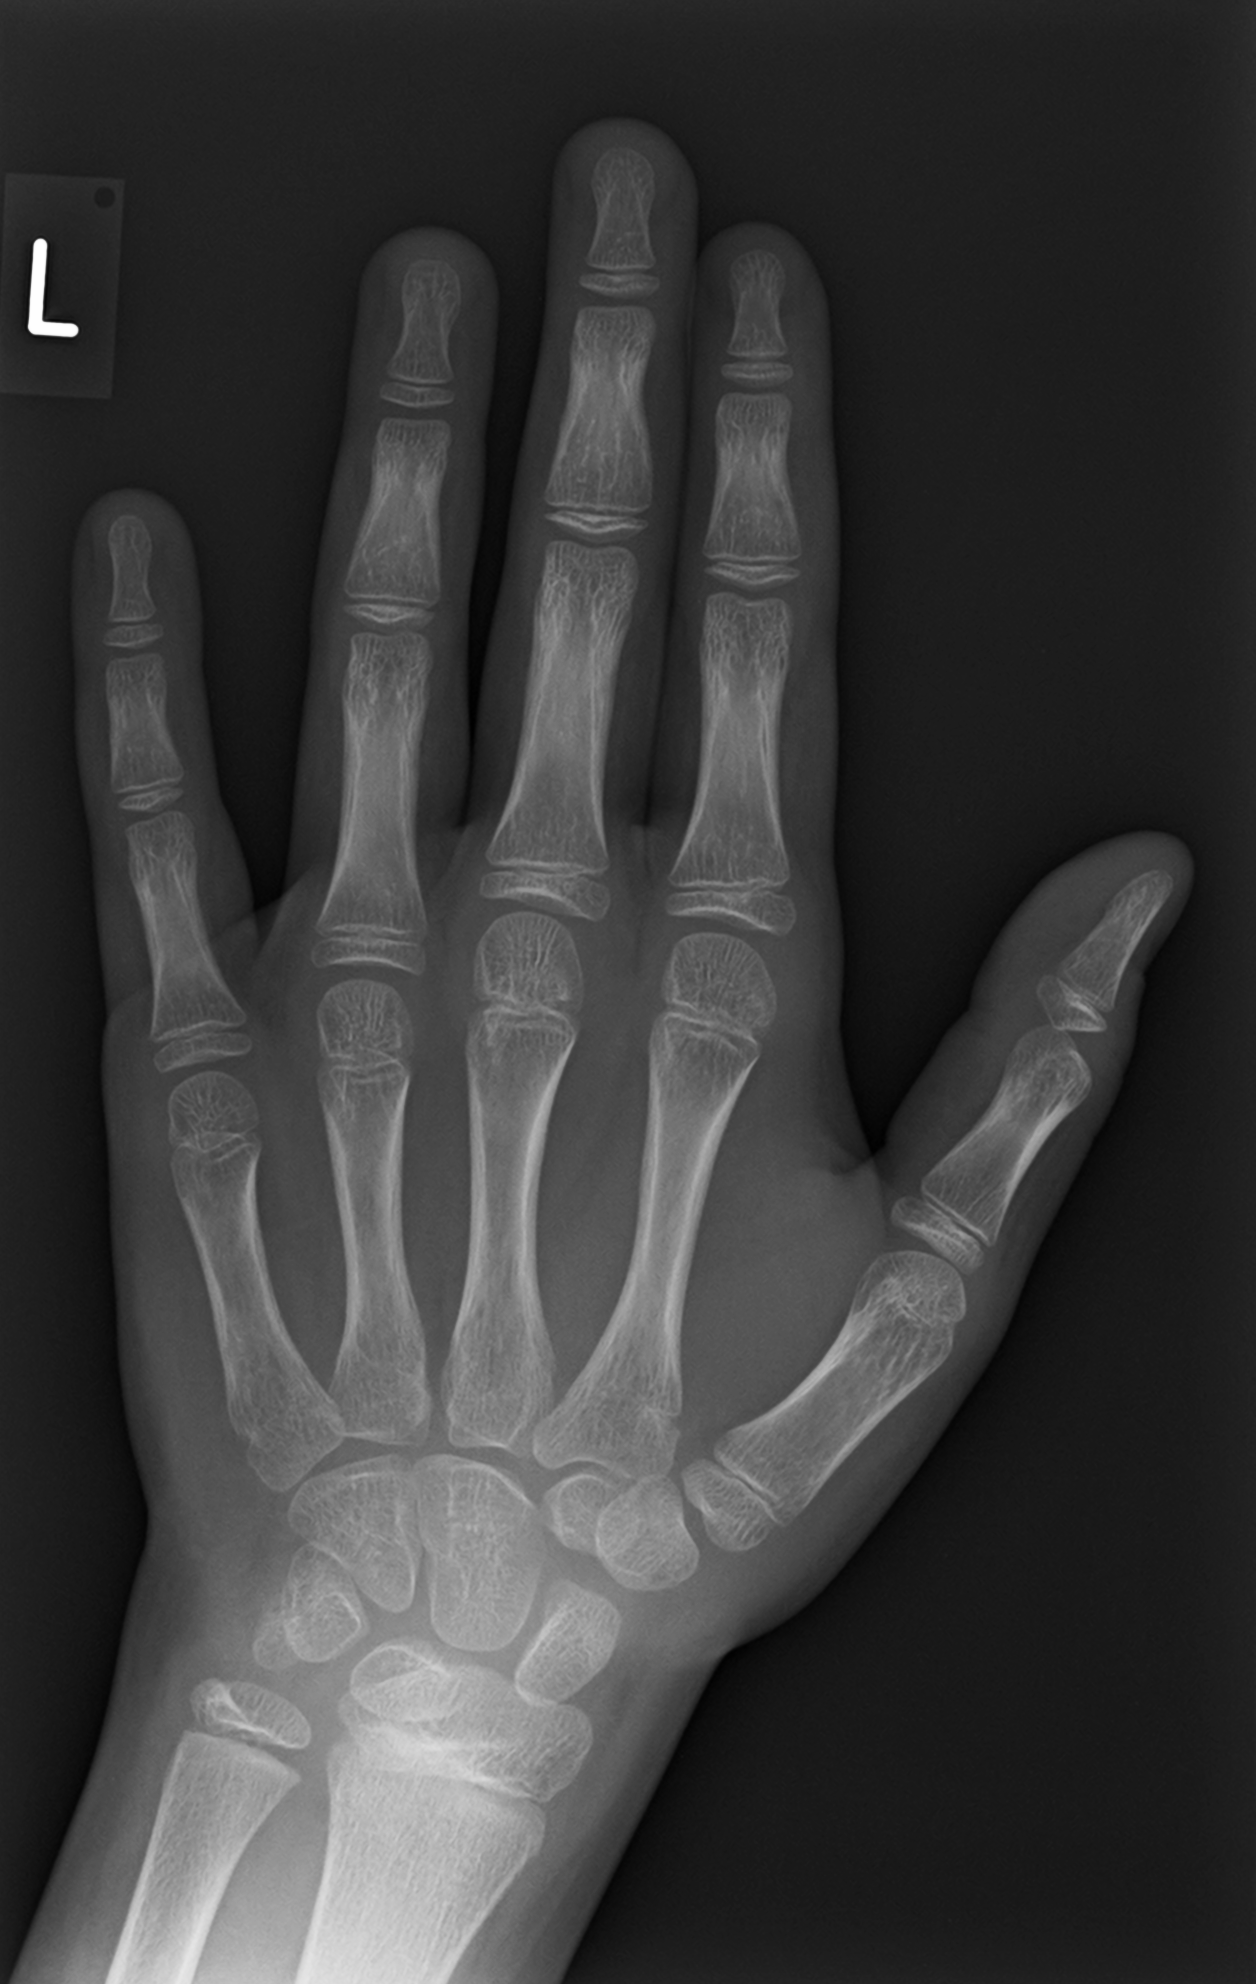

Effective sparse representation of X-Ray medical images

High sparsity in the representation of X-Ray medical images is achieved by: (a) Creating a large redundant dictionary of suitable elements for the image decomposition in the wavelet domain and (b) Applying effective strategies for selecting the particular elements which enable the sparse decomposition of the wavelet coefficients.